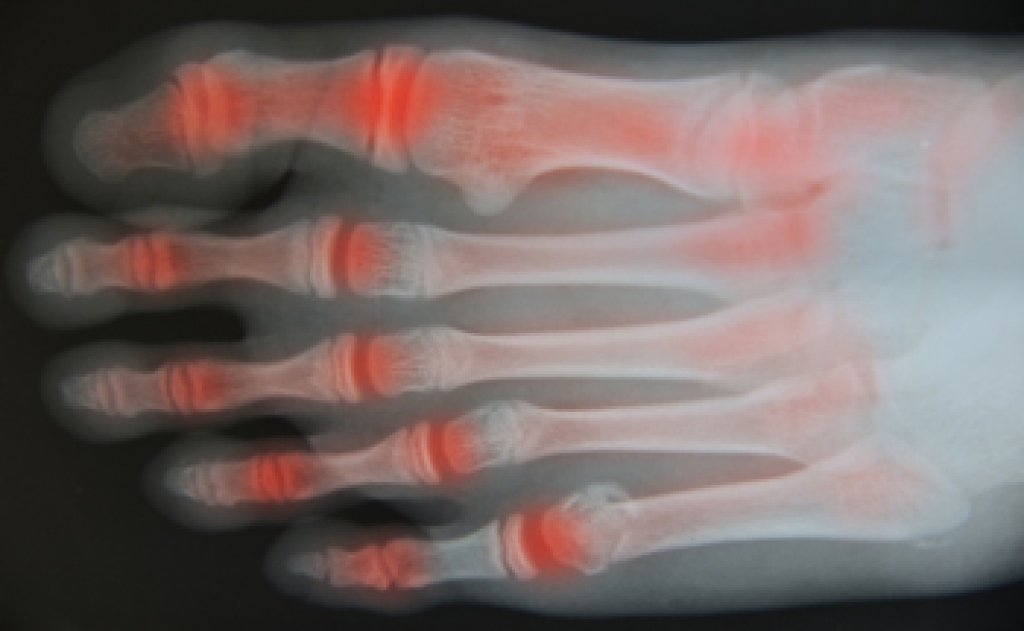

Osteoarthritis and Its Impact on Foot Health

Osteoarthritis is a degenerative joint condition that occurs when cartilage wears down over time, leading to pain and stiffness. In the feet, it often affects joints in the toes and midfoot, making walking uncomfortable. Causes include aging, excess body weight, genetic predisposition, and other forms of arthritis that contribute to joint damage. Symptoms include pain, swelling in foot joints, reduced flexibility, and discomfort that may worsen at night. Persistent foot pain can interfere with daily activities and overall quality of life. A podiatrist can diagnose the condition, recommend supportive footwear, provide custom orthotics, and develop a treatment plan to reduce pain and improve mobility. If you are experiencing ongoing foot discomfort or swelling, it is suggested that you consult a podiatrist who can offer effective relief and management solutions.

Arthritic Foot Care

Arthritis is a term that is commonly used to describe joint pain. The condition itself can occur to anyone of any age, race, or gender, and there are over 100 types of it. Nevertheless, arthritis is more commonly found in women compared to men, and it is also more prevalent in those who are overweight. The causes of arthritis vary depending on which type of arthritis you have. Osteoarthritis for example, is often caused by injury, while rheumatoid arthritis is caused by a misdirected immune system.

Symptoms

- Swelling

- Pain

- Stiffness

- Decreased Range of Motion

Arthritic symptoms range in severity, and they may come and go. Some symptoms stay the same for several years but could potentially get worse with time. Severe cases of arthritis can prevent its sufferers from performing daily activities and make walking difficult.